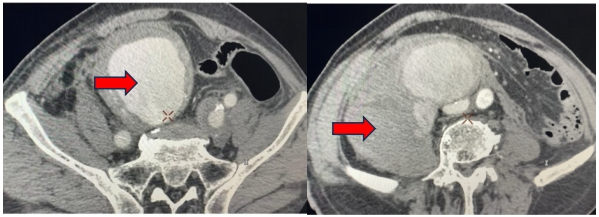

复查CTA提示动脉瘤隔绝满意

术后患者因为急性心衰、急性肾衰等,即刻转入重症医学科继续抢救,经多学科联合会诊(泌尿外科、普外科、肾内科、心内科、重症医学科)后,优化了诊疗方案,在全体医护人员共同努力下,2天后患者顺利转至普通病房继续康复治疗,患者生命体征平稳,肌酐下降至接近正常,复查CT增强无动脉瘤内漏表现,一周后顺利出院。